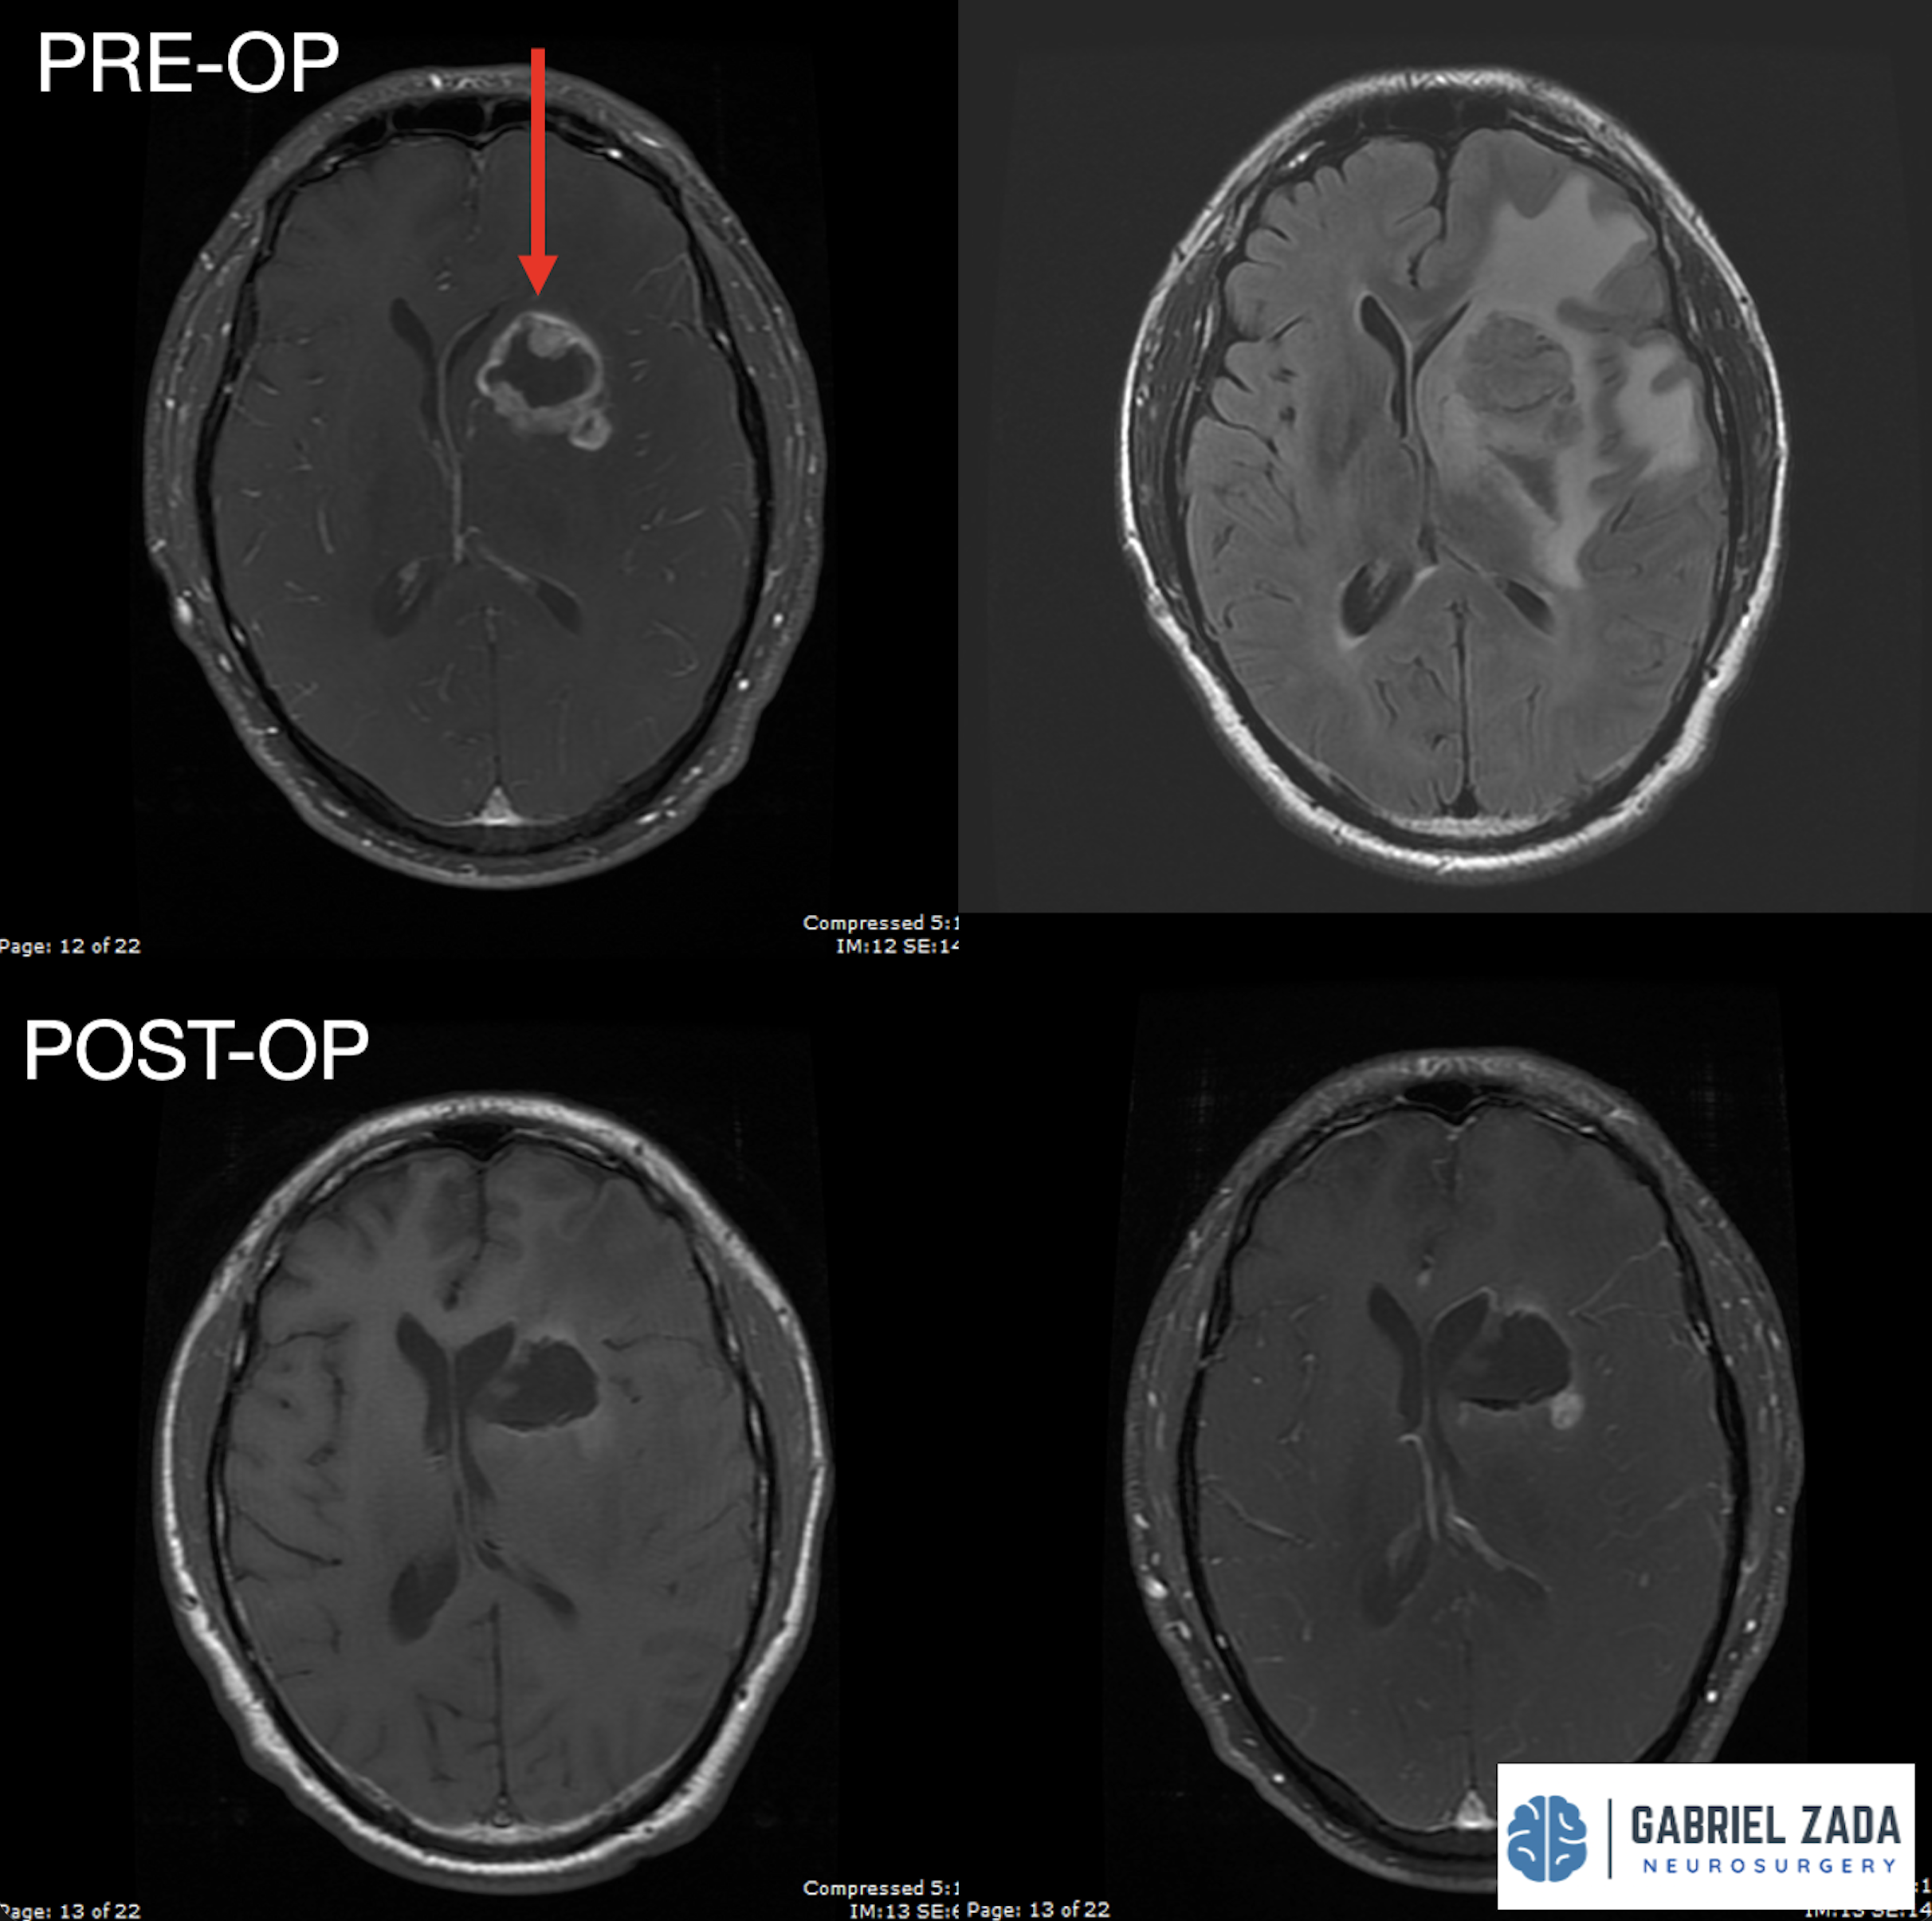

Explore this comprehensive gallery featuring pre‑ and post‑operative imaging of patients with skull‑base tumors treated by Gabriel Zada, MD, MS, FAANS, FACS. These cases highlight Dr. Zada’s expertise in advanced neurosurgical techniques and outcomes.

*Representative cases shown for educational purposes. All images de-identified. Individual results vary.